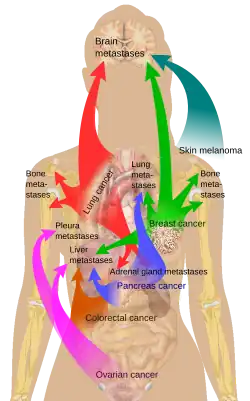

Initially, nearby lymph nodes are struck early.[10] The lungs, liver, brain, and bones are the most common metastasis locations from solid tumors.[10]

Metastatic tumors are very common in the late stages of cancer. The spread of metastasis may occur via the blood or the lymphatics or through both routes. The most common sites of metastases are the lungs, liver, brain, and the bones.[10]

Metastasis involves a complex series of steps in which cancer cells leave the original tumor site and migrate to other parts of the body via the bloodstream, via the lymphatic system, or by direct extension. To do so, malignant cells break away from the primary tumor and attach to and degrade proteins that make up the surrounding extracellular matrix (ECM), which separates the tumor from adjoining tissues. By degrading these proteins, cancer cells are able to breach the ECM and escape. The location of the metastases is not always random, with different types of cancer tending to spread to particular organs and tissues at a rate that is higher than expected by statistical chance alone.[12] Breast cancer, for example, tends to metastasize to the bones and lungs. This specificity seems to be mediated by soluble signal molecules such as chemokines[13] and transforming growth factor beta.[14] The body resists metastasis by a variety of mechanisms through the actions of a class of proteins known as metastasis suppressors, of which about a dozen are known.[15]

Organ-specific targets

There is a propensity for certain tumors to seed in particular organs. This was first discussed as the seed and soil theory by Stephen Paget in 1889.[28] The propensity for a metastatic cell to spread to a particular organ is termed 'organotropism'. For example, prostate cancer usually metastasizes to the bones. In a similar manner, colon cancer has a tendency to metastasize to the liver. Stomach cancer often metastasises to the ovary in women, when it is called a Krukenberg tumor.[29]

According to the seed and soil theory, it is difficult for cancer cells to survive outside their region of origin, so in order to metastasize they must find a location with similar characteristics.[30] For example, breast tumor cells, which gather calcium ions from breast milk, metastasize to bone tissue, where they can gather calcium ions from bone. Melanoma spreads to the brain, presumably because neural tissue and melanocytes arise from the same cell line in the embryo.[31]

In 1928, James Ewing challenged the seed and soil theory, and proposed that metastasis occurs purely by anatomic and mechanical routes. This hypothesis has been recently utilized to suggest several hypotheses about the life cycle of circulating tumor cells (CTCs) and to postulate that the patterns of spread could be better understood through a 'filter and flow' perspective.[32] However, contemporary evidences indicate that the primary tumour may dictate organotropic metastases by inducing the formation of pre-metastatic niches at distant sites, where incoming metastatic cells may engraft and colonise.[26] Specifically, exosome vesicles secreted by tumours have been shown to home to pre-metastatic sites, where they activate pro-metastatic processes such as angiogenesis and modify the immune contexture, so as to foster a favourable microenvironment for secondary tumour growth.[26]